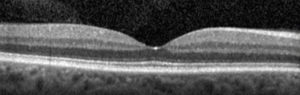

oct1